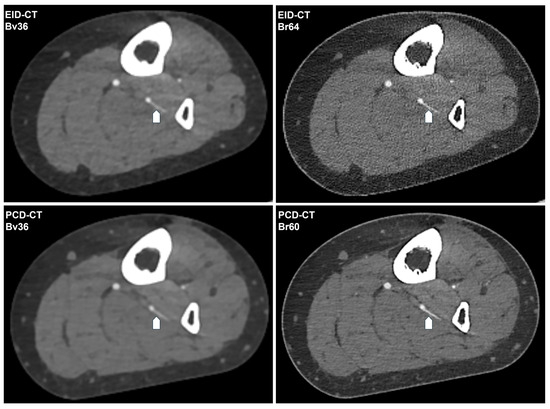

Photon-Counting CT Angiography Enables Superior Preoperative Perforator Depiction for Fibular Transplant Surgery Requiring Less Contrast Agent Compared to Energy-Integrating CT

by Ramin Saam Dazeh, Jan-Lucca Hennes, Tobias Prester, Viktor Hartung, Henner Huflage, Andreas Vollmer, Thorsten Alexander Bley, Philipp Gruschwitz and Kristina Krompaß

Diagnostics 2026, 16(5), 798; https://doi.org/10.3390/diagnostics16050798 (registering DOI) - 8 Mar 2026

Background/Objectives: The objective of this study was to ascertain whether photon-counting CT angiography (PCD-CTA) can optimize image quality for the visualization of perforating arteries for planning fibular transplant procedures in comparison to energy-integrating CT angiography (EID-CTA). Methods: In this retrospective single-center study, all patients who underwent preoperative CT of the peripheral runoff for planning between October 2021 and July 2023 were consecutively included. PCD-CTA was performed in standard resolution mode as 55 keV images with 90 mL of iodine-containing contrast agent or alternatively, an EID-CTA as a low-kV scan with 110 mL of contrast agent. The raw data were reformatted using comparable soft vascular and sharp regular convolution kernels, slice thickness/increment, and field of view. Contrast-to-noise ratio was calculated for objective image quality. Subjective evaluation was based on a rating by three radiologists using a five-point Likert scale (criteria: overall image quality, luminal attenuation, vessel sharpness, and perforator depiction). Results: Of the 26 patients who were screened, 9 could be included in each group, while 8 were excluded due to incomplete reconstructions. The reduction in contrast agent dose resulted in a non-significant decrease in luminal attenuation on PCD-CTA (452.5 ± 53.6 HU vs. 465.5 ± 99.6 HU; p = 0.375). The image noise was considerably lower for PCD-CTA (21.1 ± 1.0 HU vs. 32.9 ± 1.6 HU; p < 0.001). This resulted in a significantly higher contrast-to-noise ratio (CNR) for sharp kernel reconstructions (22.4 ± 3.5 vs. 14.5 ± 3.8; p < 0.001). No significant differences were observed for the soft vascular kernel. Subjective evaluation revealed a significant enhancement in overall image quality, vascular sharpness, and perforator depiction for PCD-CTA with sharp reconstructions. In contrast, soft kernel reconstructions and luminal attenuation demonstrated no substantial difference. Interrater agreement was good to excellent. Conclusions: PCD-CTA with sharp kernel reformatting has been demonstrated to yield superior image quality and perforator delineation of the fibular artery in comparison to standard EID-CTA. Full article

Show Figures

Figure 1